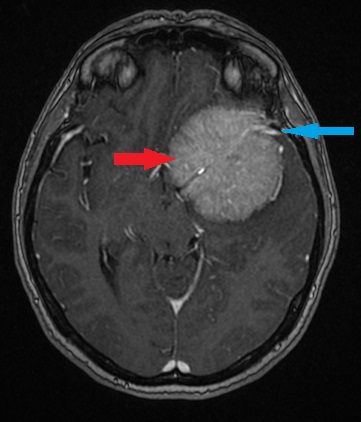

Cechy, które mogą budzić większą czujność

Zgodnie z wytycznymi European Association of Neuro-Oncology (EANO), pewne cechy w MRI mogą sugerować bardziej agresywne zachowanie guza:

- rozległy obrzęk mózgu,

- niejednorodne („plamiste”) wzmocnienie po kontraście.

Nie oznacza to automatycznie nowotworu złośliwego, ale zwykle wymaga dokładniejszej oceny i ostrożniejszego planowania leczenia.